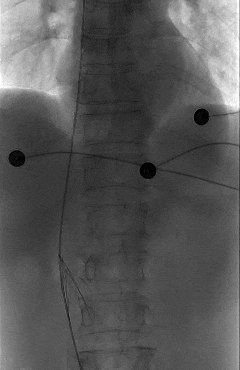

一切准备就绪后,田轩带领介入诊疗团队为阿婆实施下腔静脉滤器取出术。

术中,团队在影像设备的精准引导下,娴熟操作介入器械,精准定位倾斜的滤器,避开血管周边组织,逐步完成滤器的调整、抓取与取出操作。